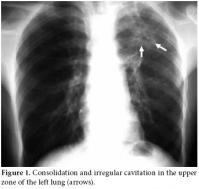

Consolidation and irregular cavitation in the upper zone of the left lung was detected in the chest radiograph (Figure 1); however, knee radiographs were considered normal. Magnetic resonance imaging of the right knee revealed inflammation in the knee, around the joint and in the superior tibiofibular articulation. The knee MRI also revealed centrally necrotic abscesses with peripheral enhancement of the rim after a gadolinium injection (Figure 2). An MRI of the right shoulder also showed increased inflammatory signal changes in the acromioclavicular joint and adjacent soft tissue with enhancement after gadolinium injection (Figure 3). The purified protein derivative (PPD) skin test for Tbc measured 22 mm. A synovial biopsy taken from the knee detected granulomatous inflammation with caseation necrosis. Antibiotic treatment with isoniazid, rifampicin, ethambutol and pyrazinamide were prescribed for two months followed by rifampicin and isoniazid for seven months. The patient showed significant improvement in the knee and shoulder within two months and close to complete improvement within six months.

Magnetic resonance imaging is the best modality to evaluate soft tissue affection by demonstrating marrow changes, joint effusion, synovitis, pannus, and cartilage and bone erosions.[2,16] Joint and periarticular involvement and lesions are particularly well defined by an MRI. The definitive diagnosis is performed from a positive mycobacterial culture and a histological examination of synovial fluid or synovial membranes. An examination of a biopsy specimen is an important and useful diagnostic method. Amplifying DNA of Mycobacterium tuberculosis from synovial fluid or bone by PCR could be useful for the early diagnosis of Tbc. We performed a definitive diagnosis through the histopathological examination of a synovial biopsy, a chest radiograph showing cavitation and the definitive demonstration on MRI examination. This was done in spite of the lack of positivity of mycobacterial culture and PCR. In addition, following the initiation of specific antituberculous treatment, the patient showed significant improvement in the knee and shoulder within two months with close to complete improvement within six months. We extended treatment to nine months in accordance with the recommendations for musculoskeletal tuberculosis in the literature and by the Turkey Ministry of Health.[17,18]